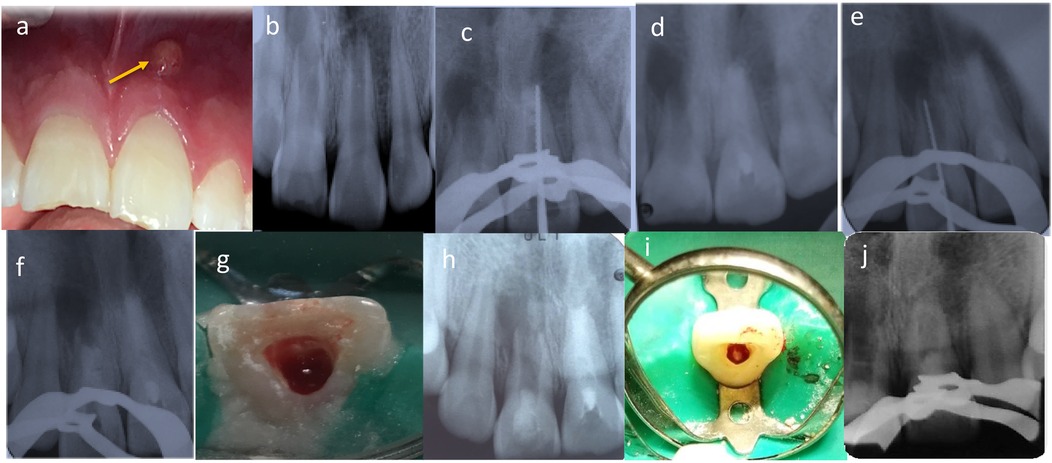

At the current examination, diagnostic methods included clinical inspection, pulp sensibility testing with cold stimulus, periapical radiographs, and cone beam CT. In addition, fistula tract tracing with a gutta-percha cone was performed in tooth 2.1, which presented a vestibular parulis. Clinical findings also revealed enamel–dentin fractures on teeth 1.1 and 2.1, with tooth 1.1 showing a slight vestibular displacement (Figure 1a). Both teeth were non-responsive to cold pulp testing. Radiographic evaluation, together with the fistula tract tracing in tooth 2.1, confirmed incomplete root formation and extensive periapical radiolucencies in both teeth (Figure 1b).

Figure 1. (a) Intraoral clinical examination revealed a vestibular parulis related to tooth 2.1. (b) Radiological assessment detected incomplete root formation of teeth 1.1 and 2.1. (c,d) tooth 2.1 first treatment session, determination of working length, instrumentation, and medication with CaOH (ultracal XS, Ultradent). (e,f) tooth 1.1 first treatment session, determination of working length, instrumentation, and medication with CaOH (ultracal XS, Ultradent). (g) RE of tooth 1.1. Apical bleeding was induced, forming a clot 3–4 mm below the CEJ. (h) Cervical area of tooth 1.1 was sealed with a bioceramic cement (Biodentine, Septodont), and the access was sealed with glass ionomer. (i) RE of tooth 2.1. The patient was asymptomatic, with a healed sinus tract. Apical bleeding was induced to form the blood clot. (j) Cervical area of tooth 2.1 was sealed with a bioceramic cement (Biodentine, Septodont), and the access was sealed with glass ionomer.

The initial treatment session focused on tooth 2.1. Local infiltration anesthesia with 2% mepivacaine (Scandonest 2%, Septodont, France) was administered. The access cavity was prepared and abundantly irrigated with 1.5% sodium hypochlorite, and a radiographic length control with a N° 80K-file (Dentsply Maillefer, Ballaigues, Switzerland) was taken (Figure 1c). The working length was established by a second radiography taken 3 mm shorter than the apparent tooth length, and final irrigation was completed with saline solution. The canal was dried with sterile paper points No. 80 (Dentsply Maillefer, Ballaigues, Switzerland), and calcium hydroxide paste (UltraCal XS, Ultradent Products, Inc., South Jordan, UT, USA) was applied as intracanal medication. The access was sealed with a sterile cotton pellet, temporary cement (Fermin, Detax GmbH & Co. KG, Ettlingen, Germany), and glass ionomer cement (Chemfil, Dentsply Sirona, Charlotte, NC, USA) (Figure 1d).

The following day, treatment of tooth 1.1 commenced using the same protocol (Figures 1e,f). Both teeth remained medicated for one month.

At the second appointment, one month later, the patient was asymptomatic (Figure 2a). Treatment continued with tooth 1.1, which was anesthetized with 3% mepivacaine (Scandicaine, Septodont, France). The temporary restoration and intracanal medication were removed with abundant irrigation using 1.5% sodium hypochlorite, followed by 3 ml of saline and 20 ml of 17% EDTA. After drying with sterile paper points, apical bleeding was induced with a No. 60K-file (Dentsply Maillefer, Ballaigues, Switzerland) to promote blood clot formation 3–4 mm below the CEJ (Figure 1g). The cervical third was sealed with bioceramic cement (Biodentine, Septodont, France), and the access was closed with glass ionomer cement (Chemfil, Dentsply Sirona, Charlotte, NC, USA) (Figure 1h).

One week later, the regenerative endodontic treatment of tooth 2.1 was completed. The patient remained asymptomatic, with no sinus tract or exudate in the root canal. Local anesthesia with 3% mepivacaine (Scandicaine, Septodont, France) was administered. The same protocol was followed (Figure 1i,j).